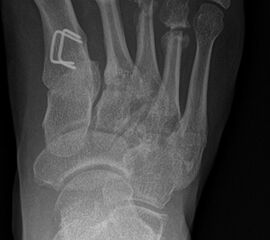

Zusätzlich schränken Wachstumsfugen die Wahl der Osteosynthese ein. Eine die Fuge kreuzende Osteosynthese ist ausschließlich mit Kirschner-Drähten möglich (Abb. 3).

Abb. 3 a-j: Beispiel einer Calcaneusverschiebeosteotomie mit offenen Wachstumsfugen und der entsprechenden Osteosynthese mit Kirschner Drähten. Lokalisation der Osteotomie (a), Lage der Fräse (b-d), Drahtlage mehrere Ansichten (e-h), Heilung der Osteotomie 4 Wochen postoperativ und Entfernung der Drähte (i-j).

Zum Lesen der Bildbeschreibung und zur Vollansicht bitte die Bilder anklicken. Bilder: A. Helmers.